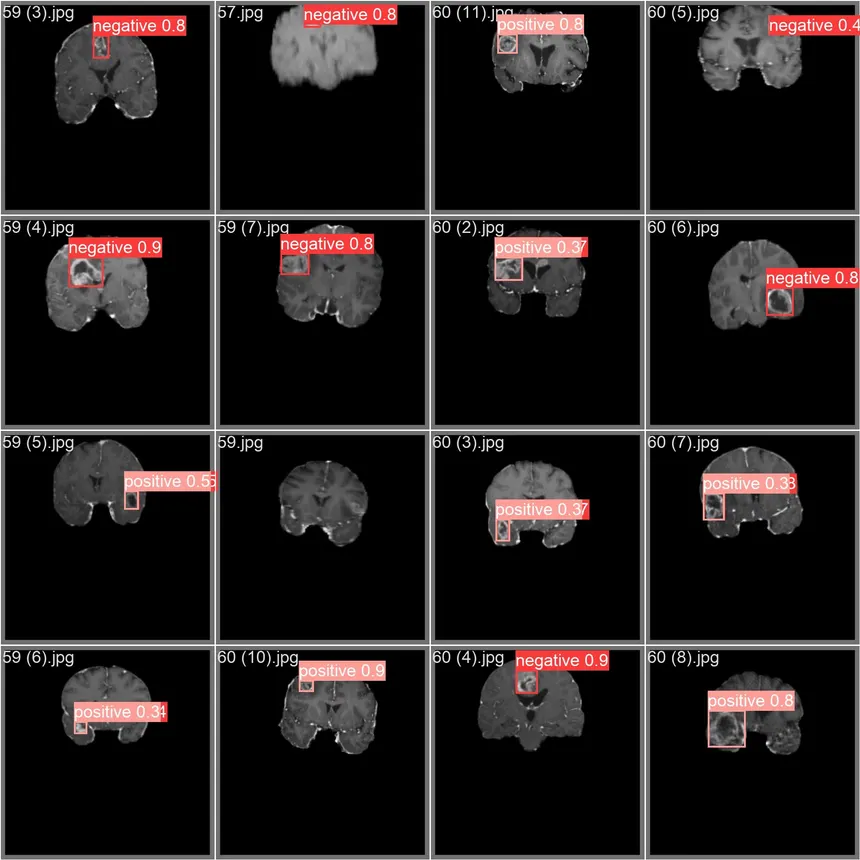

التنبؤ بأورام الدماغ (الرؤية الحاسوبية)

هذا المشروع عبارة عن أداة تصوير وتشخيص طبي عالية الدقة، تم تطويرها باستخدام تقنيات متقدمة في مجال رؤية الحاسوب والتعلم العميق. يقوم النظام، من خلال معالجة صور الرنين المغناطيسي عبر شبكات عصبية التفافية متخصصة، بتحديد وتصنيف التشوهات العصبية، مع التركيز على الكشف الآلي عن أورام الدماغ. يُطبّق التطبيق تقنيات متطورة لتجزئة الصور واستخلاص الميزات للتمييز بين الأنسجة السليمة والأورام، مما يوفر طبقة دعم قائمة على البيانات للتحليل السريري. يُعد هذا المشروع مثالًا بارزًا على كيفية استخدام الذكاء الاصطناعي في الرعاية الصحية لتحسين دقة التشخيص وتقليل الوقت اللازم لمراجعة الصور الطبية، مُبرزًا الخبرة في معالجة البيانات البيولوجية الحساسة وعالية الأبعاد.